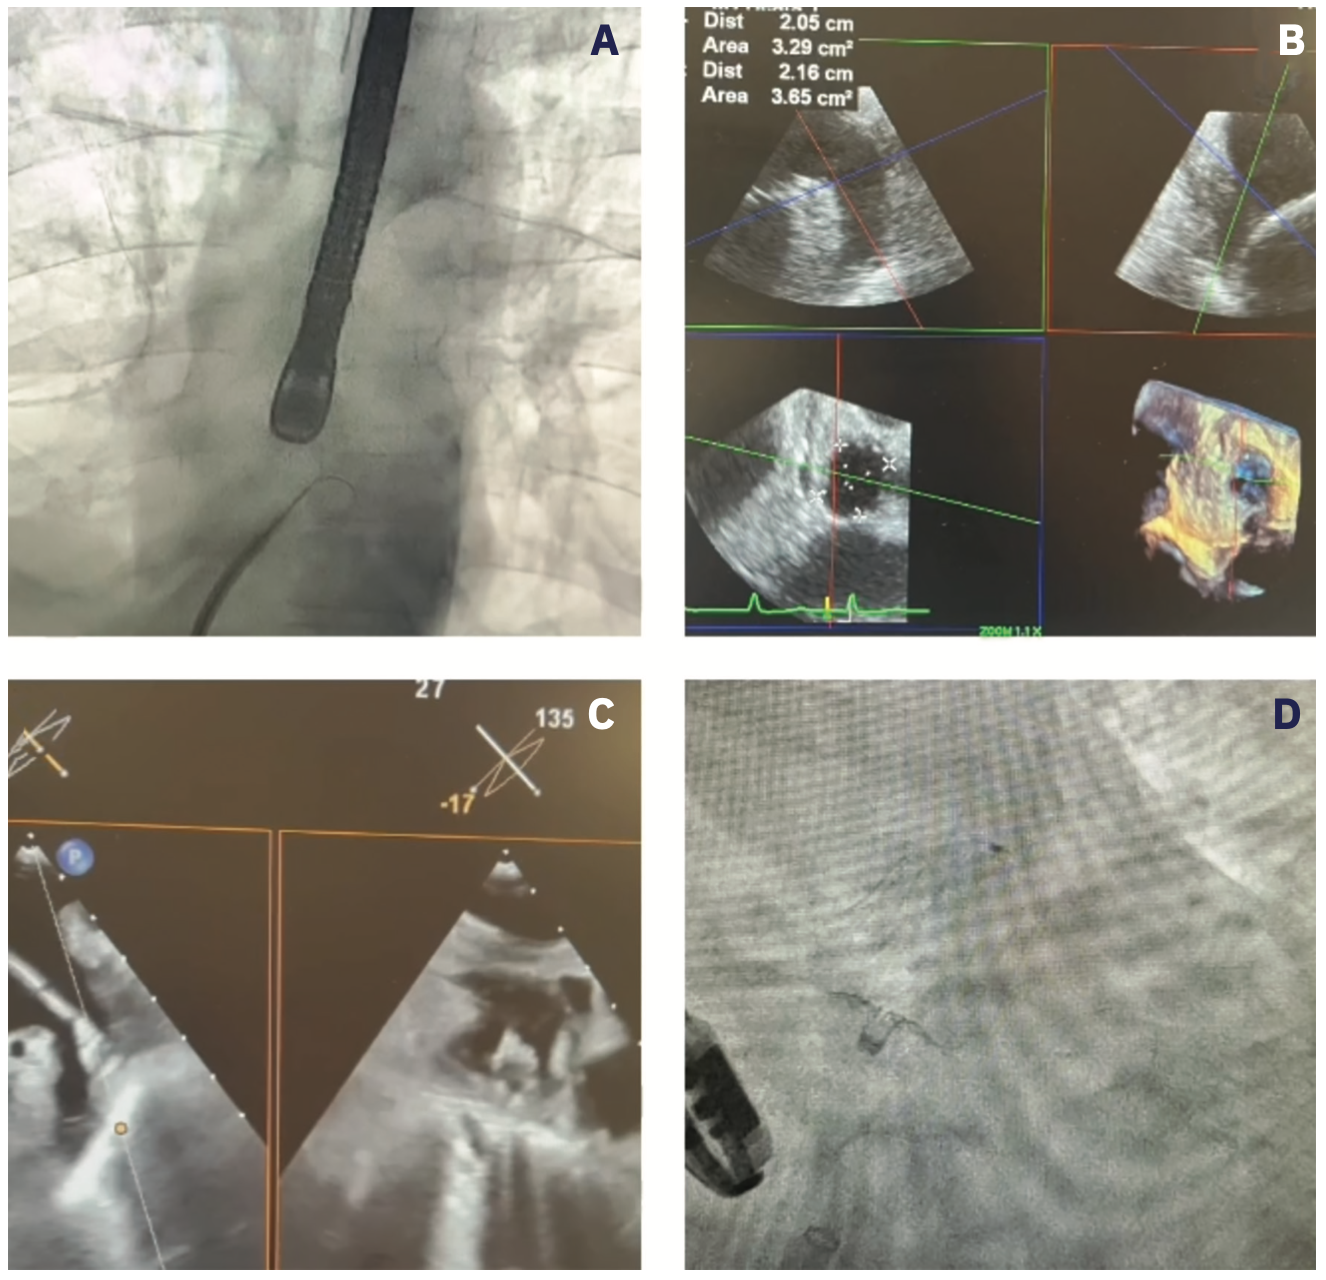

Candidates for Amulet occluder implant are selected in the same manner as described above. TEE use, hemostasis, and transseptal access vary; however, they generally mirror the same practices outlined. The Amplatzer Steerable Delivery Sheath became commercially available in the United States in April 2022. Measurement of the LAA orifice, landing zone, and desired depth help determine choice of the appropriate lobe size (Figure 4A).

The device is unsheathed to a “ball” position (Figure 4B), which allows for rotational movement. Once proper coaxial alignment is obtained with the sheath and ball, forward pressure can be applied to transition the device from the “ball” to an intermediate configuration of “triangle” if more depth is required. The triangle configuration allows for the force at the tip of the device to be radially distributed, thereby making advancement safer. Once the “ball” or “triangle” is in the correct position, the lobe is deployed with concomitant unsheathing and forward pressure.

The body of the lobe should be two-thirds past the circumflex artery, with some compression within the LAA, and oriented perpendicular to the long access of the LAA. Next, the sheath is retracted to expose the disc and create separation between the lobe (Figure 4C). The disc should not excessively overlay the coumadin ridge of the pulmonary vein and mitral valve, respectively. If the orientation is suitable and the tug test stable, the device is released.

Dual antiplatelet therapy is administered postoperatively, and our general practice is to obtain a TEE (Figure 4D) or CT at the 6-month mark for medication de-escalation.